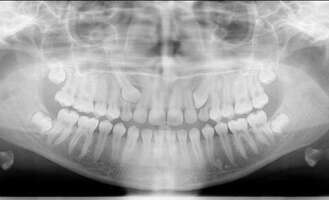

Traitement réalisé chez une jeune fille de 11ans à l’aide d’un appareil multi-attache esthétique. Après avoir nivelé les incisives, la patiente a porté des tractions élastiques inter-arcades afin d’améliorer l’emboitement des deux arcades. La durée du traitement a été de 23 mois.